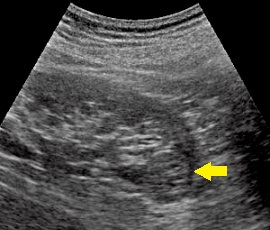

超音波画像